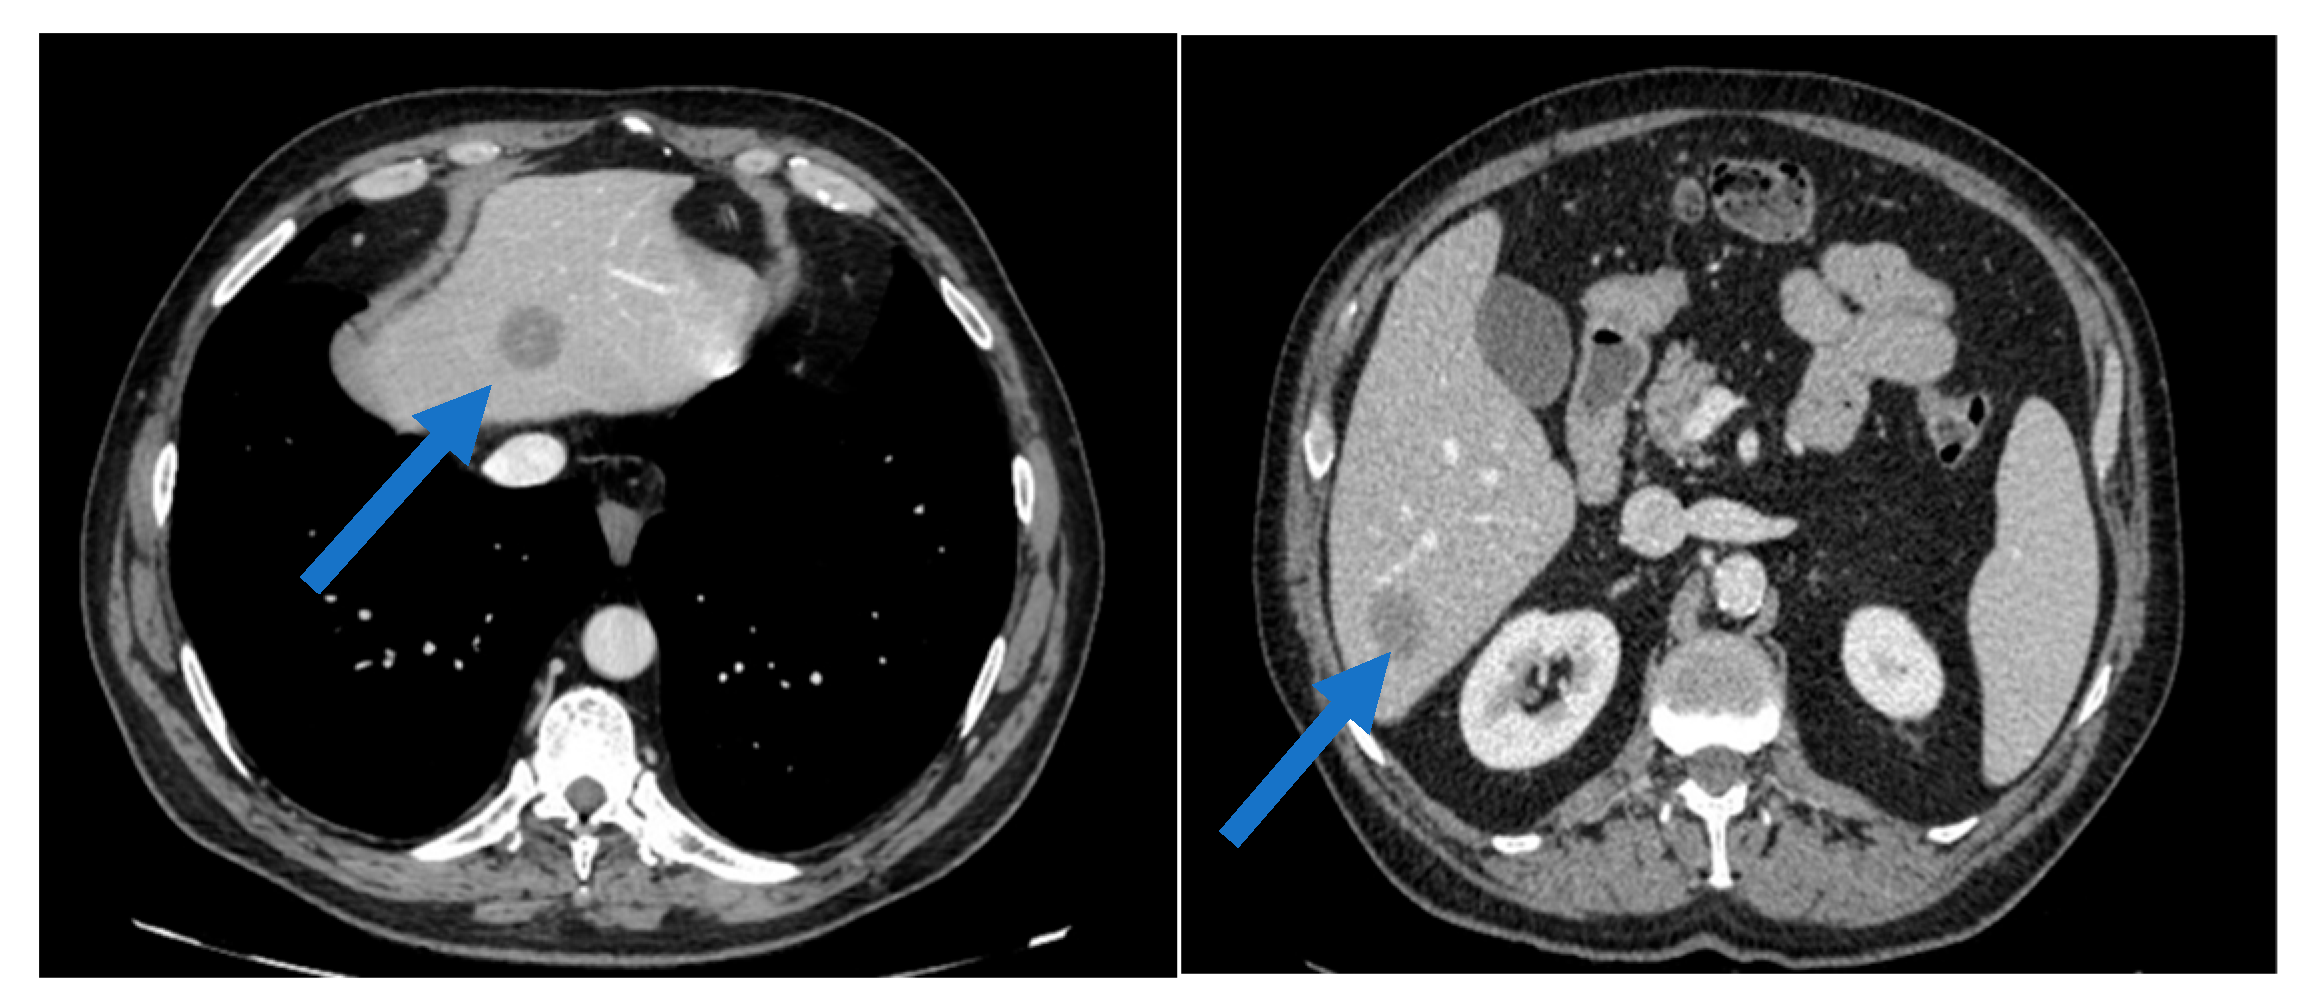

Clinical Course of Parotid Carcinoma with Hepatic and Nodal Metastases: A Case Report

2. Case Presentation